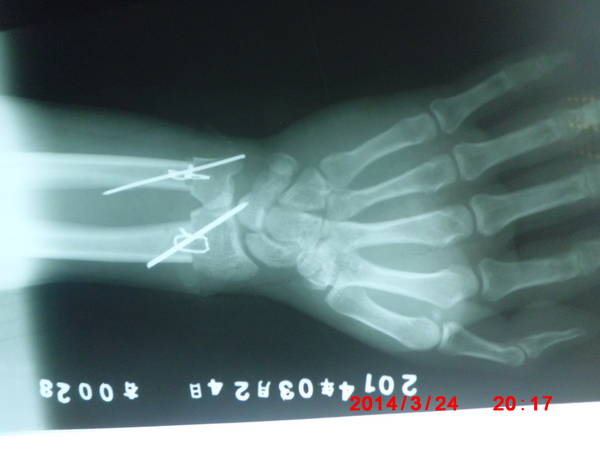

[断指再植] 一例断臂

骨头怎么固定的/

斯氏针加钢丝